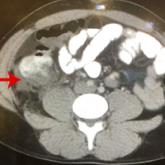

Gone but Not Forgotten: Acute Appendicitis Postappendectomy